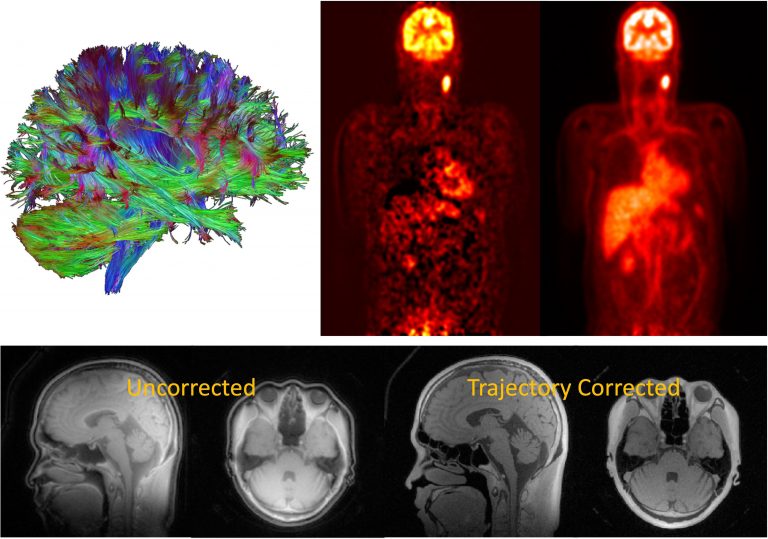

Image Reconstruction and Data Modeling

We develop and apply sophisticated models for measured data to reconstruct higher-quality images. Our approaches incorporate physiological information into dynamic datasets, enabling us to extract new quantitative insights. Key research topics include:

- Iterative Reconstruction Algorithms: Improving image quality and reducing artifacts, especially in challenging scenarios like low-dose imaging.

- Statistical Modeling: Creating accurate models of image data to handle incomplete or noisy measurements.

- Machine Learning-Based Techniques: Leveraging deep learning to enhance reconstruction accuracy and speed.

- Motion-Robust Reconstruction: Developing methods to correct for patient movement, ensuring clearer and more reliable imaging results.

These techniques are beneficial in clinical and research settings where data quality may be compromised by noise, motion, or limited sampling.

Magnetic Resonance Imaging (MRI)

We explore the frontiers of MRI technology, with a particular focus on designing and optimizing novel pulse sequences and radiofrequency (RF) coils.

- Pulse Sequence Development: Pulse sequences are patterns of RF pulses and magnetic field gradients that manipulate nuclear spins. By customizing these sequences, we can selectively highlight different tissue properties, improve image contrast, and reduce scan times.

- RF Coil Design: RF coils are essential for transmitting and receiving signals in MRI systems. We create specialized coil designs to improve signal sensitivity and overall image quality.

Positron Emission Tomography (PET)

Our PET research focuses on novel methodologies and techniques to improve sensitivity, resolution, and diagnostic utility. PET imaging involves the use of radioactive tracers that highlight metabolic processes in the body. By integrating PET with other imaging modalities, we gain a more comprehensive view of disease processes:

- PET/CT and PET/MRI: Combining PET with CT or MRI offers both functional and structural information, enhancing diagnostic accuracy.

- Methodology and Technique Development: We design advanced acquisition protocols and data analysis methods to capture more detailed information about physiological and molecular processes.